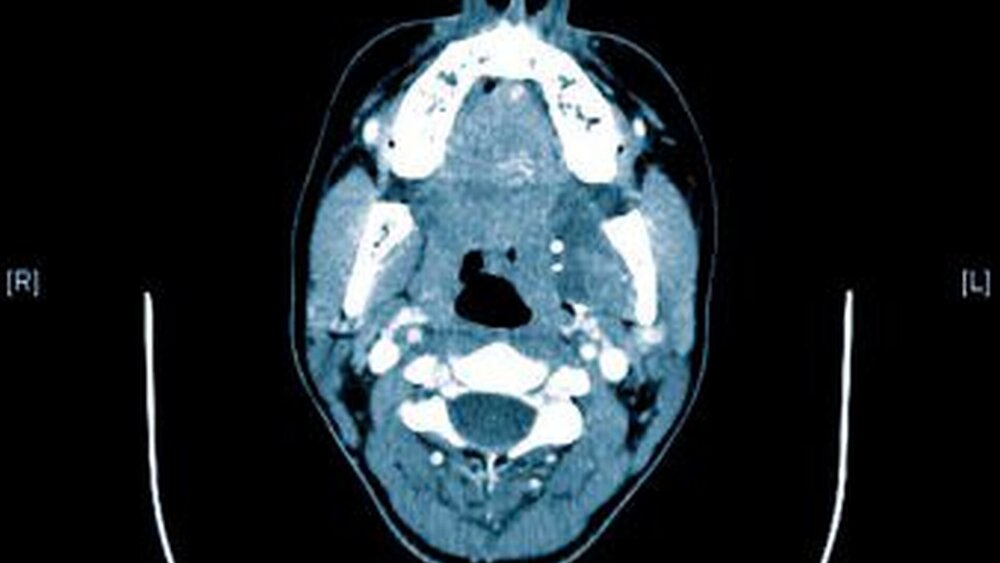

Zur genauen räumlichen Zuordnung der Verschattungen unterhalb der Incisurae semilunares wurde eine dentale digitale volumentomografische Untersuchung durchgeführt (Abbildungen 2 bis 4).